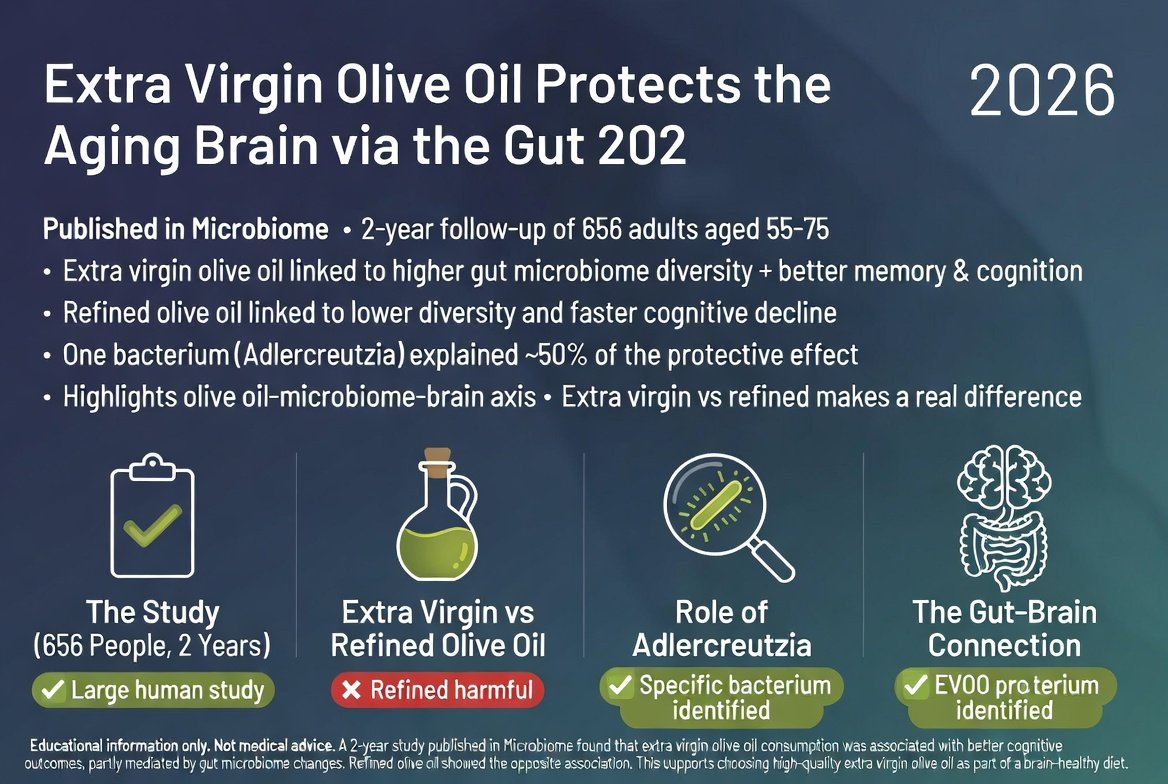

כולם יודעים ששמן זית בריא ללב, אבל מחקר חדש שפורסם בכתב העת Microbiome חושף נתיב מפתיע: שמן זית כתית מגן על המוח המזדקן לא רק ישירות, אלא דרך המעי. במ...